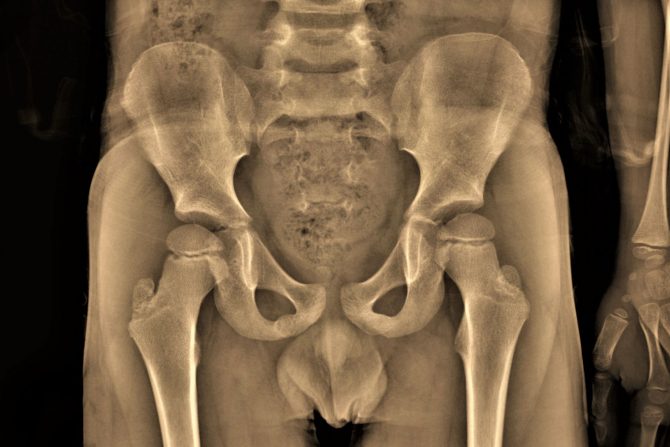

Kada se na osnovu opisanih simptoma obavi fizički pregled i uradi anamneza, sledi radiografija karlice sa kukovima. Na osnovu još nekih laboratorijskih testova krvi, postavlja se dijagnoza i utvrđuje stepen oštećenja.